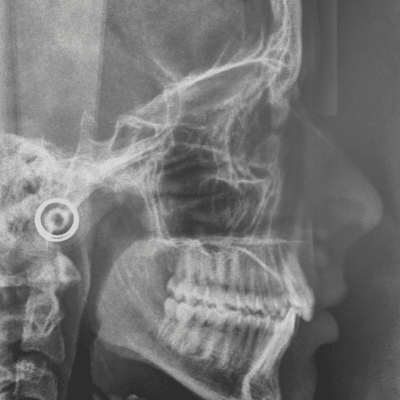

At every regularly-scheduled dental exam, the dentist will look inside a patient’s mouth to check the teeth for cavities or signs of other problems. However, there are parts of the teeth and mouth that a dentist can’t see with his eyes alone. Dentists rely on x-ray images to determine the health of the bone and areas of the teeth they would not otherwise be able to see.

X-rays show teeth that have not yet erupted or become visible in the mouth. Dentists use x-rays to make sure permanent teeth are developing normally and to check for missing teeth. They may use x-rays to determine if a patient is likely to need orthodontic treatment in the future. Dentists can also see impacted teeth, like wisdom teeth, and determine if they require intervention.

While a dentist can examine the gums visually, he cannot see the bone that supports the teeth and gums. Bone health is critical to maintaining good oral health. Dental x-rays show the level and density of the bone structure that supports the teeth. This helps the dentist to determine if the patient needs any special gum treatments. X-rays also help a dentist to determine if a patientpatient’ss healthy enough to support certain dental treatments, like implants.

While rare, a patient can develop tumors or cysts in the jaw bone. A dentist can use a special kind of x-ray, called a panoramic x-ray, to check the entire jaw for abnormal growth.

When preparing for complex dental procedures, such as root canals, extractions, or orthodontic treatments, x-rays provide vital information about the internal structures of the mouth. They help dentists map out the precise location of teeth roots, assess bone density, and identify potential complications. This detailed insight ensures that procedures are as effective and minimally invasive as possible, improving patient outcomes and recovery times.